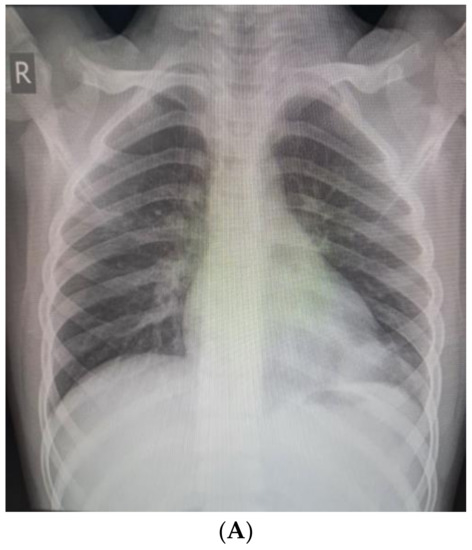

The patient’s complaints persisted, and the child was admitted to the Department of Pediatric Thoracic Surgery for further exams. The condition of the child was stable, with reduced productive cough and reduced vesicular breathing paravertebrally and axillary on the left side of the chest. His hemodynamic was stable, and his abdomen was not tender, without hepatosplenomegaly. Blood and biochemical tests were in the normal range, with slightly increased inflammation markers (leucocytes 11.8 G/L, hemoglobin 137 g/L, hematocrit 0.43 L/L, thrombocytes 404 G/L, CRP 0.59 mg/dL, ASAT 21 U/L, ALAT 13 U/L, creatinine 53 µmol/L). Frontal and chest X-rays revealed atelectasis of the posterior basal segment (Figure 2A,B). A flexible bronchoscopy was performed. The trachea, right main bronchus, and segmental and subsegmental bronchi were without obstruction and pathology. The left main and upper lobe bronchi also were normal. A thick secretion was found in the left lower lobe bronchus, and a bronchoalveolar lavage was performed. Stenosis and obturation resulting from hypergranulation were found in the segmental and subsegmental bronchi of the posterior basal segment (LB10). Recanalization of the LB10 was performed with histopathology and microbiology samples. After five days, a second flexible bronchoscopy was made. Poor improvement was marked by persisting stenosis and obturation of LB10. Again, a biopsy and recanalization with new samples were performed. The microbiology was negative, and the histology showed acute bronchitis. Antibiotics (Ceftriaxone) and symptomatic treatment (Pulmicort inhalations) were extended during the entire hospital stay. The patient was discharged on the 7th day and transferred back to the Department of Pediatric Pulmonology for prolonged treatment.

Figure 2. (A). Frontal chest X-ray—atelectasis of the posterior basal segment. (B). Lateral chest X-ray.